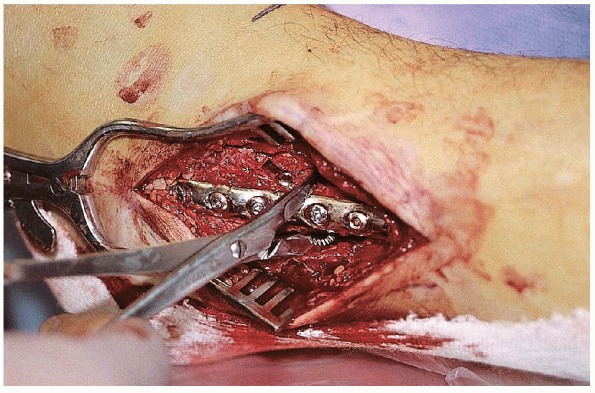

![]()  |

FIGURE 33-14. A to C:

Lateral plate placement with screw insertion proximally and distally. The most distal screw is usually inserted first and angled proximally. D and E: Fluoroscopic evaluation after plate insertion.  |